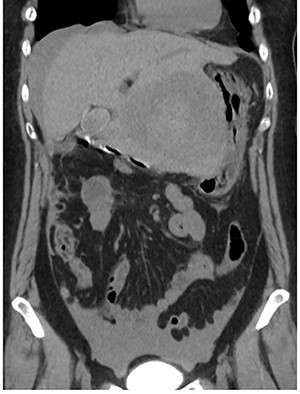

A 56-year-old woman presented to another hospital with acute abdomen. Computed tomography (CT) examination demonstrated a tumor 10 cm in diameter that protruded from the left lateral segment of the liver, with evidence suggestive of rupture of the liver tumor (Fig. 1). Since the patient was in good general condition, she was referred to our hospital for further evaluation. Her blood biochemical parameters when she was referred to our hospital were hemoglobin: 11.6 g/dl, albumin: 3.4 g/dl, γ-globulin: 18.5% and anti-acetylcholine receptor antibody: <0.3 nmol/L. Dynamic CT presented a liver tumor 10 cm in diameter, which was located at the left lateral segment of the liver, with a clear margin. A mass with an irregular margin was also identified in the anterior mediastinum (Fig. 2). On percutaneous angiography, since obvious extravasation of the contrast medium could not be identified, the arteries of the left lateral segment were embolized to prevent re-bleeding. Although a definitive preoperative diagnosis could not be made using magnetic resonance imaging (MRI) (Fig. 3), fluorodeoxyglucose positron emission tomography (FDG) showed increased FDG uptake in both the hepatic and anterior mediastinal tumors (Fig. 4). Although the liver tumor was suspected to be metastasis secondary to a thymoma based on the clinical findings, percutaneous tumor biopsy was performed to confirm the pathological diagnosis. The biopsy suggested malignant T-cell lymphoma or metastatic thymoma. In order to prevent re-rupture of the hepatic tumor, to confirm the pathological diagnosis and to potentially achieve a curative resection, the patient underwent laparoscopic left lateral segmentectomy (Fig. 5). Although the tumor was found to be adherent to the stomach, blunt dissection was possible. In addition, no peritoneal dissemination was detected. The surgical duration was 212 min and estimated blood loss was 50 ml. The liver tumor was pathologically diagnosed as metastatic thymoma type AB (Fig. 6). The patient’s postoperative course was uneventful and she subsequently underwent radical thymectomy 3 months after the liver resection. The thymic tumor was pathologically diagnosed as thymoma type B2. Currently, 30 months after thymectomy, she remains free from tumor recurrence.

MRI. (a) T1-weighted image: low-intensity area suggestive of intratumor hemorrhage. (b) T2-weighted image: the tumor had heterogenous intensity.

In the present case, contrast-enhanced CT demonstrated two-layered enhancement of the liver tumor. Considering the gross findings of the liver tumor, the inner layer consisted of a hematoma, and the outer layer was formed by compression of the tumor into a crescent shape by the intratumor hematoma, as seen on MRI. Since thymomas, including those that metastasize to the liver are soft, they can rupture easily and can be easily compressed by intratumor hematoma.